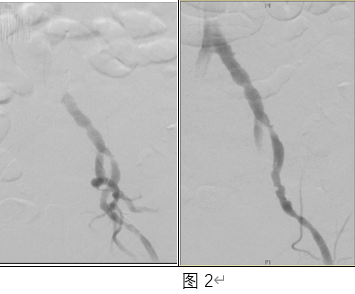

继续主动脉瘤“拆弹”手术,由于髂动脉入路血管恢复生理功能,主动脉介入操作顺滑通过,顺利完成了介入操作。术中,吴巍巍教授团队同时发现,该患者肾动脉多处狭窄,在一台手术中,为该患者完成了降主动脉、肾动脉、髂动脉等多处复杂血管病变“一站式”治疗。